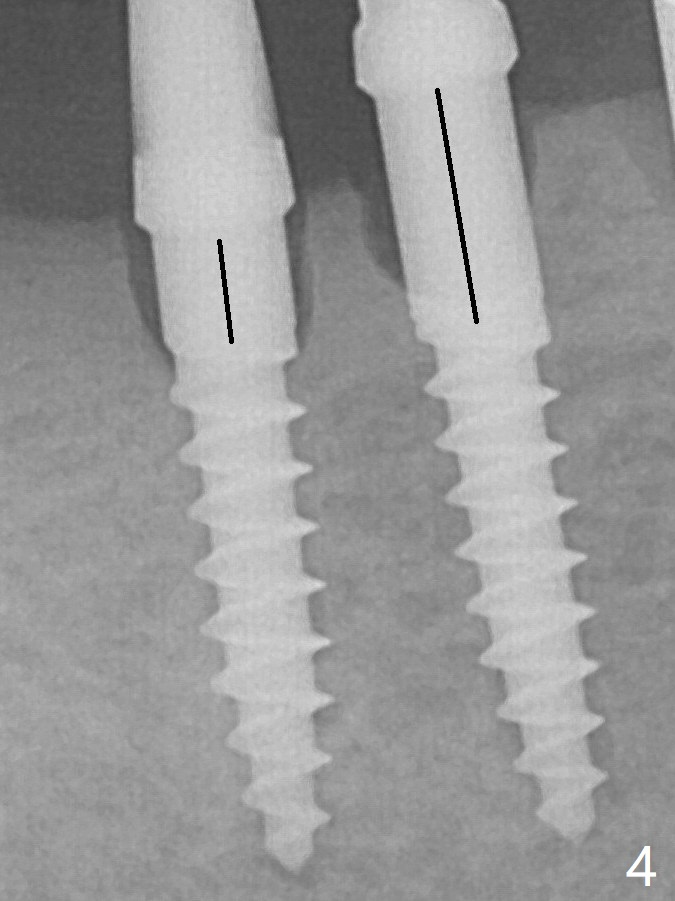

Since the mesial implant is high in occlusion, the cuff of the distal implant is changed to be 2 mm (Fig.4 (shorter black line)).  The crestal bone around the implants resorbs 5 months postop (Fig.7).